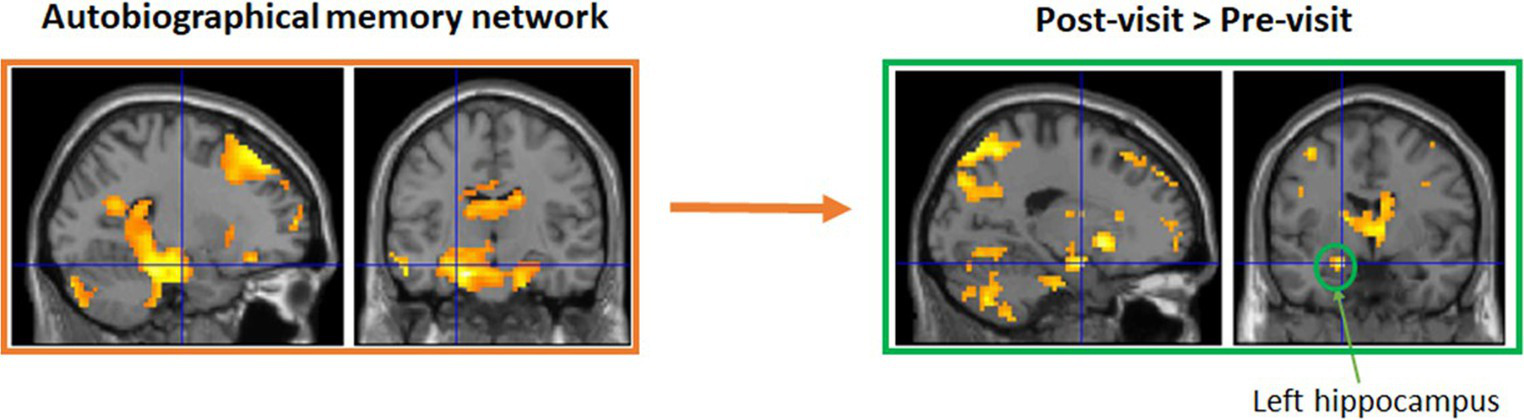

Groups in Maynooth, Swords, Tallaght, and Dublin city center all took part in 6 weeks of reminiscence. Weekly groups recalled stories on their earlier years about personal experiences and major national events, with the help of photos, such as the visit of John F Kennedy in 1963 and the Pope in 1979. While only modest improvements were observed in these groups, this is likely due to the fact that they were a cognitively very healthy group at the outset and the fact that numbers were low in each group, reducing statistical power (Allen et al., 2020, 2021a). To examine potential benefits for cognitive decline, a modified version of this intervention was administered to a small group of older adults living with dementia, with a weekly group meeting in Peamount Healthcare’s Dementia Unit. Again, measures of cognition and psychological health were taken before and after 6 weeks of reminiscence, with some indications of improvements in certain aspects of memory (Allen et al., 2021b). An additional patient experiencing Transient Epileptic Amnesia (TEA) also participated in the intervention, and again some modest improvements were observed. Functional imaging data are currently being analyzed (Viard et al., in preparation). The classical autobiographical memory network (including the precuneus, medial frontal and lateral temporal gyri, and hippocampi) was activated for pre- and post-visits separately. Direct comparisons showed greater activation for post-visit in left superior medial frontal gyrus, precuneus, and anterior hippocampus, compared to pre-visit (see Figure 1).

A small sub-group also took part in functional MRI brain scanning at Trinity College Institute of Neuroscience to test for structural and functional brain changes as a result of the intervention. Functional imaging data are currently being analyzed (Viard et al., in preparation). Initial results suggest the classical autobiographical memory network (including the precuneus, medial frontal and lateral temporal gyri, and hippocampi) was activated for pre- and post-visits separately. Direct comparisons showed greater activation for post-visit in left superior medial frontal gyrus, precuneus, and anterior hippocampus, compared to pre-visit.